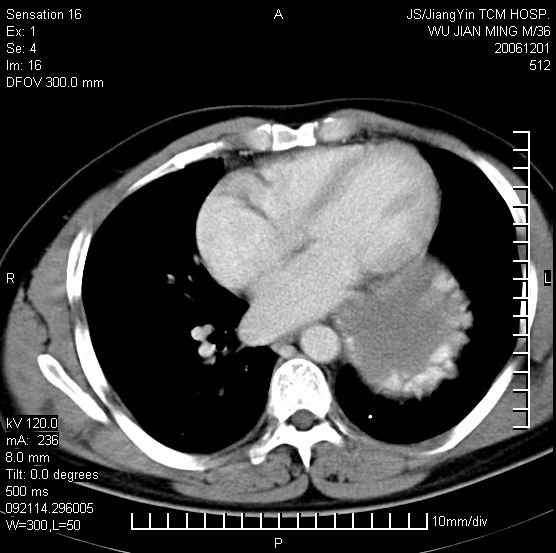

以下是引用dyqct在2006-12-1 21:17:00的发言:[br]左心缘旁及后肋膈窦区见巨大椭圆形混杂密度肿块,周围见大小不等斑片状钙化,内部无强化,周围包膜轻度强化,心脏明显受压变形,即明显占位效应,肿块广基与心包、膈相连。肝、脾内、肝门见多数小结节状钙化影。[br]考虑:1、左心缘旁及后肋膈窦区慢性包裹性胸膜炎(结核性);[br] 2、肝、脾及肝门淋巴结核已钙化。[br]

以下是引用zrs在2006-12-2 17:28:00的发言:[br]肺内、肝脾内虽有钙化,但不支持结核性胸胸膜炎包裹,而支持寄生虫感染![br][br]